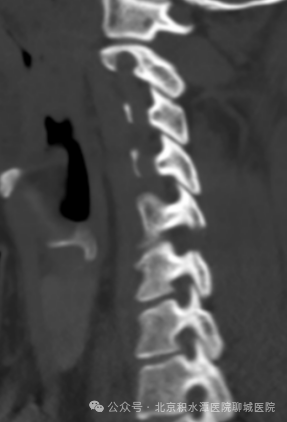

术后影像:去除C5/6左侧椎管背侧少量骨质

进行减压并摘除突出的间盘组织

术后影像:去除少量骨质扩大胸椎椎管

并取出骨化的黄韧带